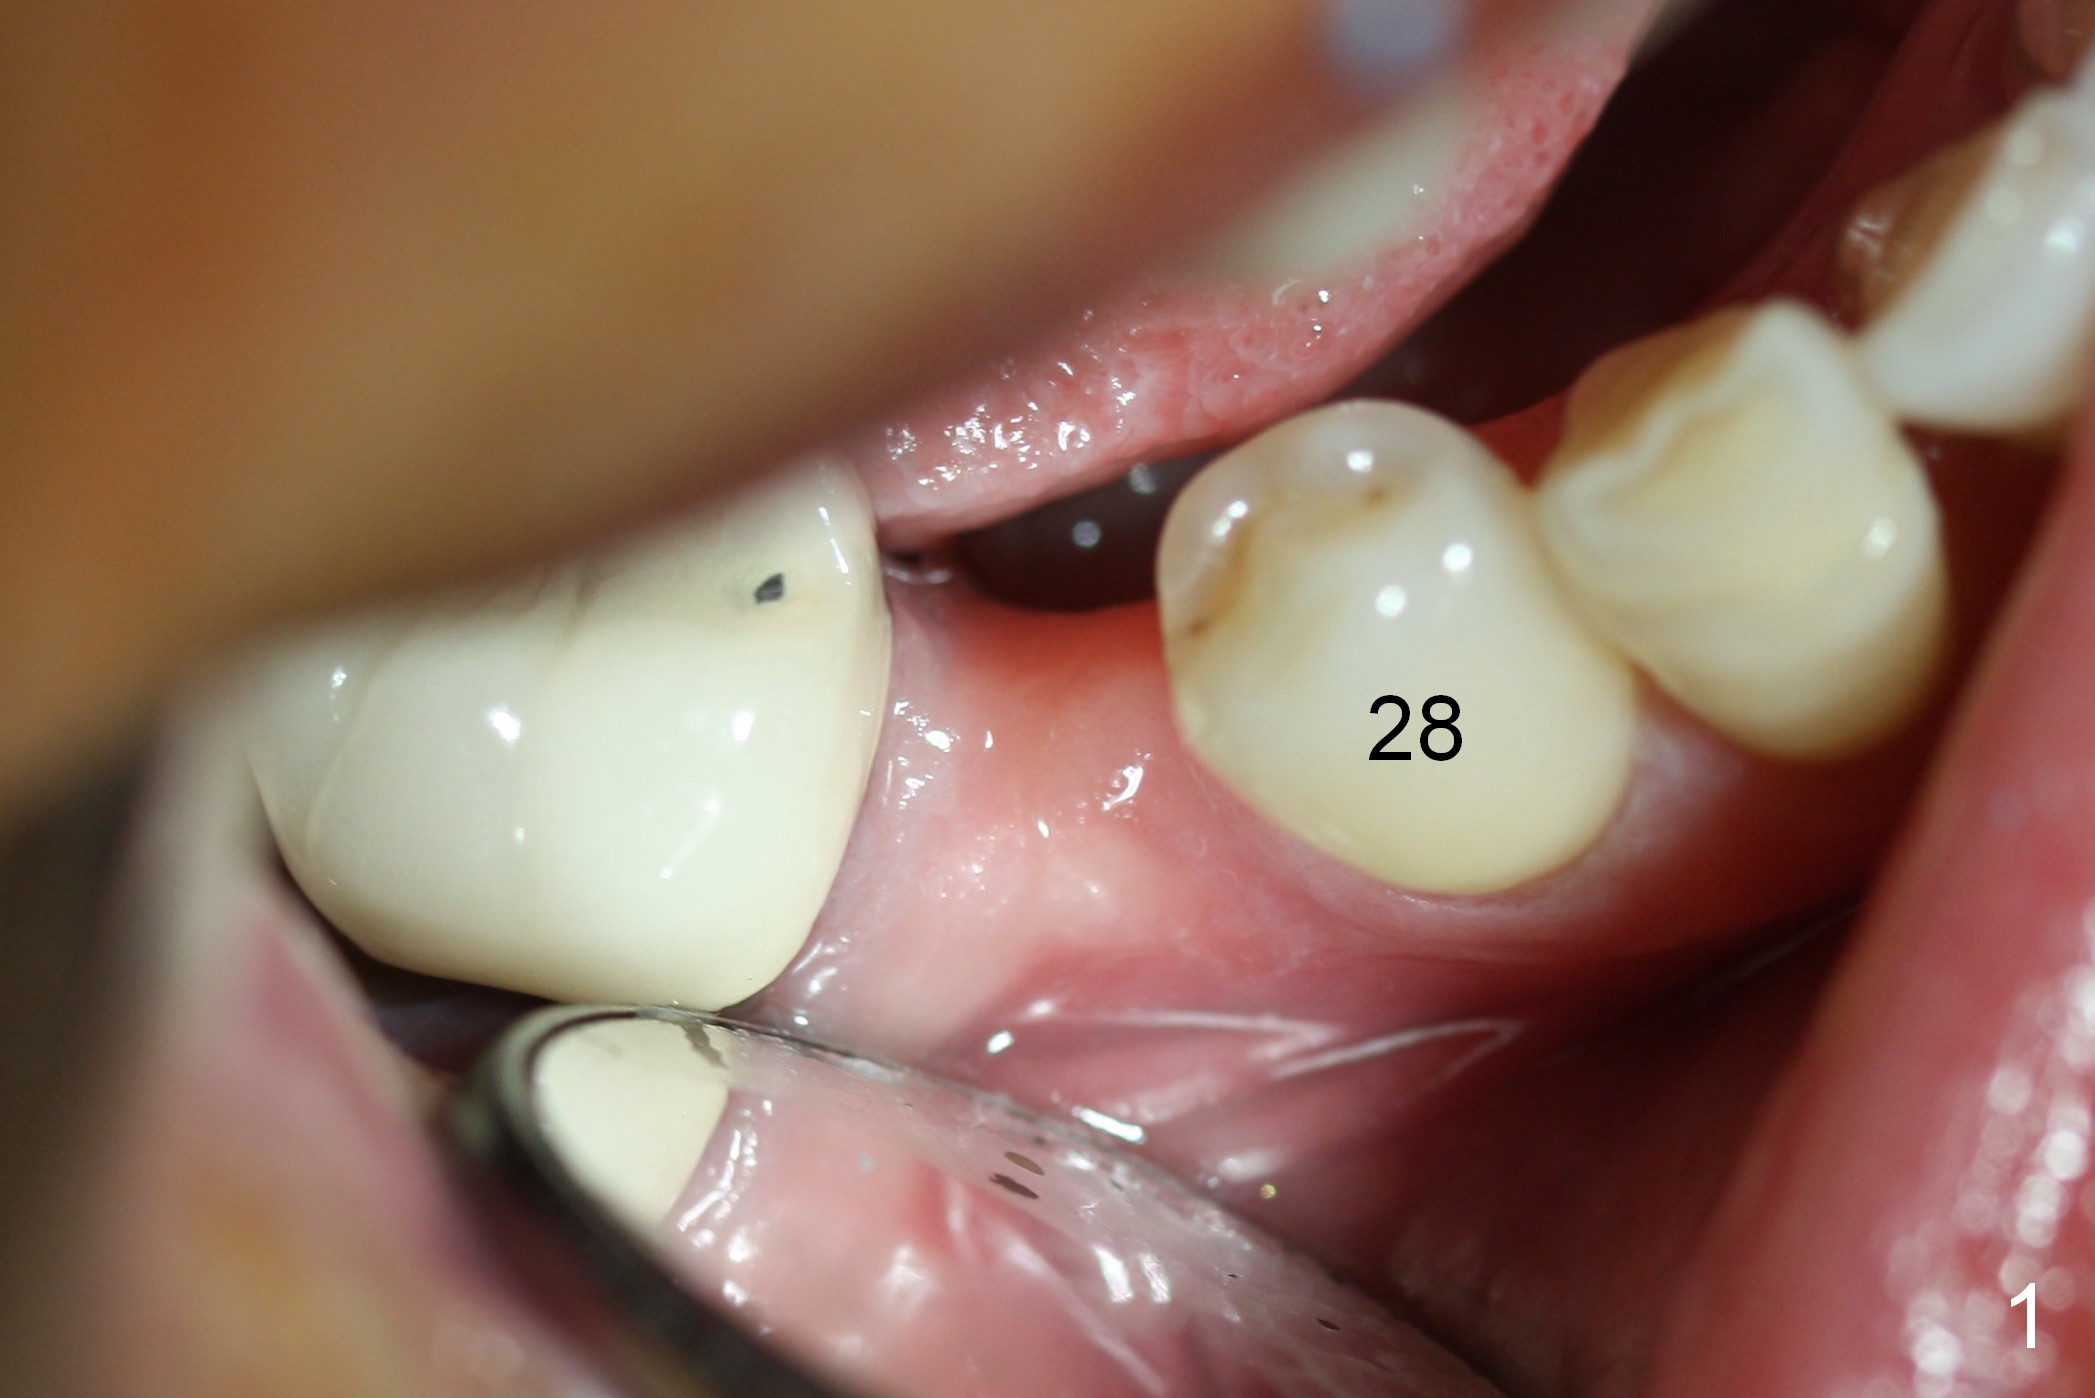

Preop photo shows the distal inclination of the tooth #28 (Fig.1). The distal surface of the latter is reduced before incision for implant placement at #29 (Fig.2). The buccolingual width is approximately 4 mm, as compared to 3 mm implant positioner (Fig.3). After 1.2x10 mm osteotomy (Fig.5), the mesiodistal cortical bone is removed with a small high-speed fissural bur (Fig.4). When a 2.5x12(2) mm 1-piece implant is placed (Fig.6), there is no buccal (Fig.7) or lingual plate perforation. There is no postop paresthesia. There is mild bone loss distal 4 months postop (Fig.8 *). Take photos before and after permanent crown cementation to show increase in ridge width after bone graft and improvement in gingival health after provisional modification. Take PA and/or BW post cementation to show that the distal bone resorption (Fig.8 *) is partially due to angulation. No continuous bone loss 15 months post cementation (Fig.9). There is mild bone resorption mesially 2 years 3 months post cementation (Fig.10). The soft and hard tissues remain healthy 4 years 3 months post cementation (Fig.11,12).